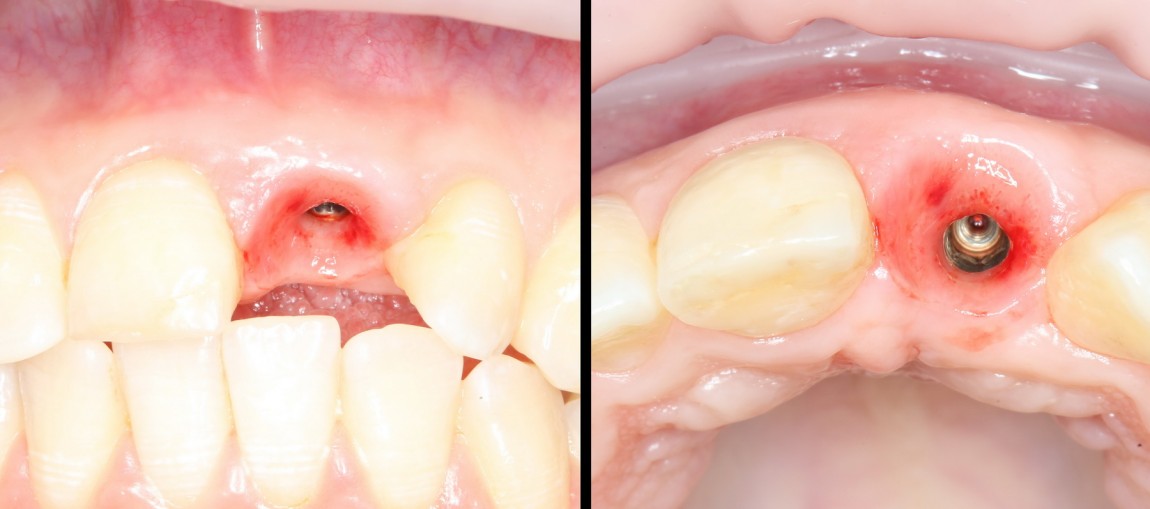

Через 3 месяца мы готовы приступить к формированию десны. И каким-то невероятным образом, у нас получился даже избыток слизистой оболочки. Что, безусловно, очень даже хорошо:

По фотографии хорошо видно, как изменилась форма альвеолярного гребня после операции.

Ответственный момент. Делаем разрез и открываем имплант:

Как видите, вестибулярная стека импланта находится в новообразованной костной ткани. А это значит, что наша остеопластика удалась. Хотя, это еще нельзя назвать результатом нашей операции.

Ставим формирователь десны. Затем, Давид окончательно формирует десну с помощью временной коронки. После его формирования слизистая выглядит примерно так:

а это уже очень близко к тому, что мы хотим получить в результате лечения. Именно поэтому не стоит игнорировать временные коронки, особенно в эстетически значимой зоне. И, особенно, в ответственных случаях.